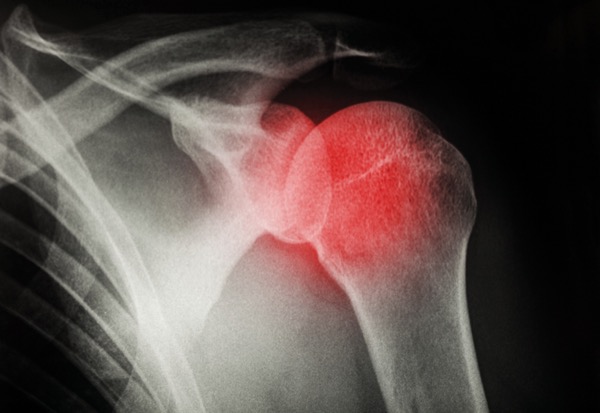

NEW YORK—In this issue, our series investigating anesthesia-related litigation reviews a case in which subpar supervision, a lack of standardized policies and procedures (or lack of knowledge of them), and poor communication led to postoperative paraplegia in a patient undergoing shoulder surgery. How could this happen?